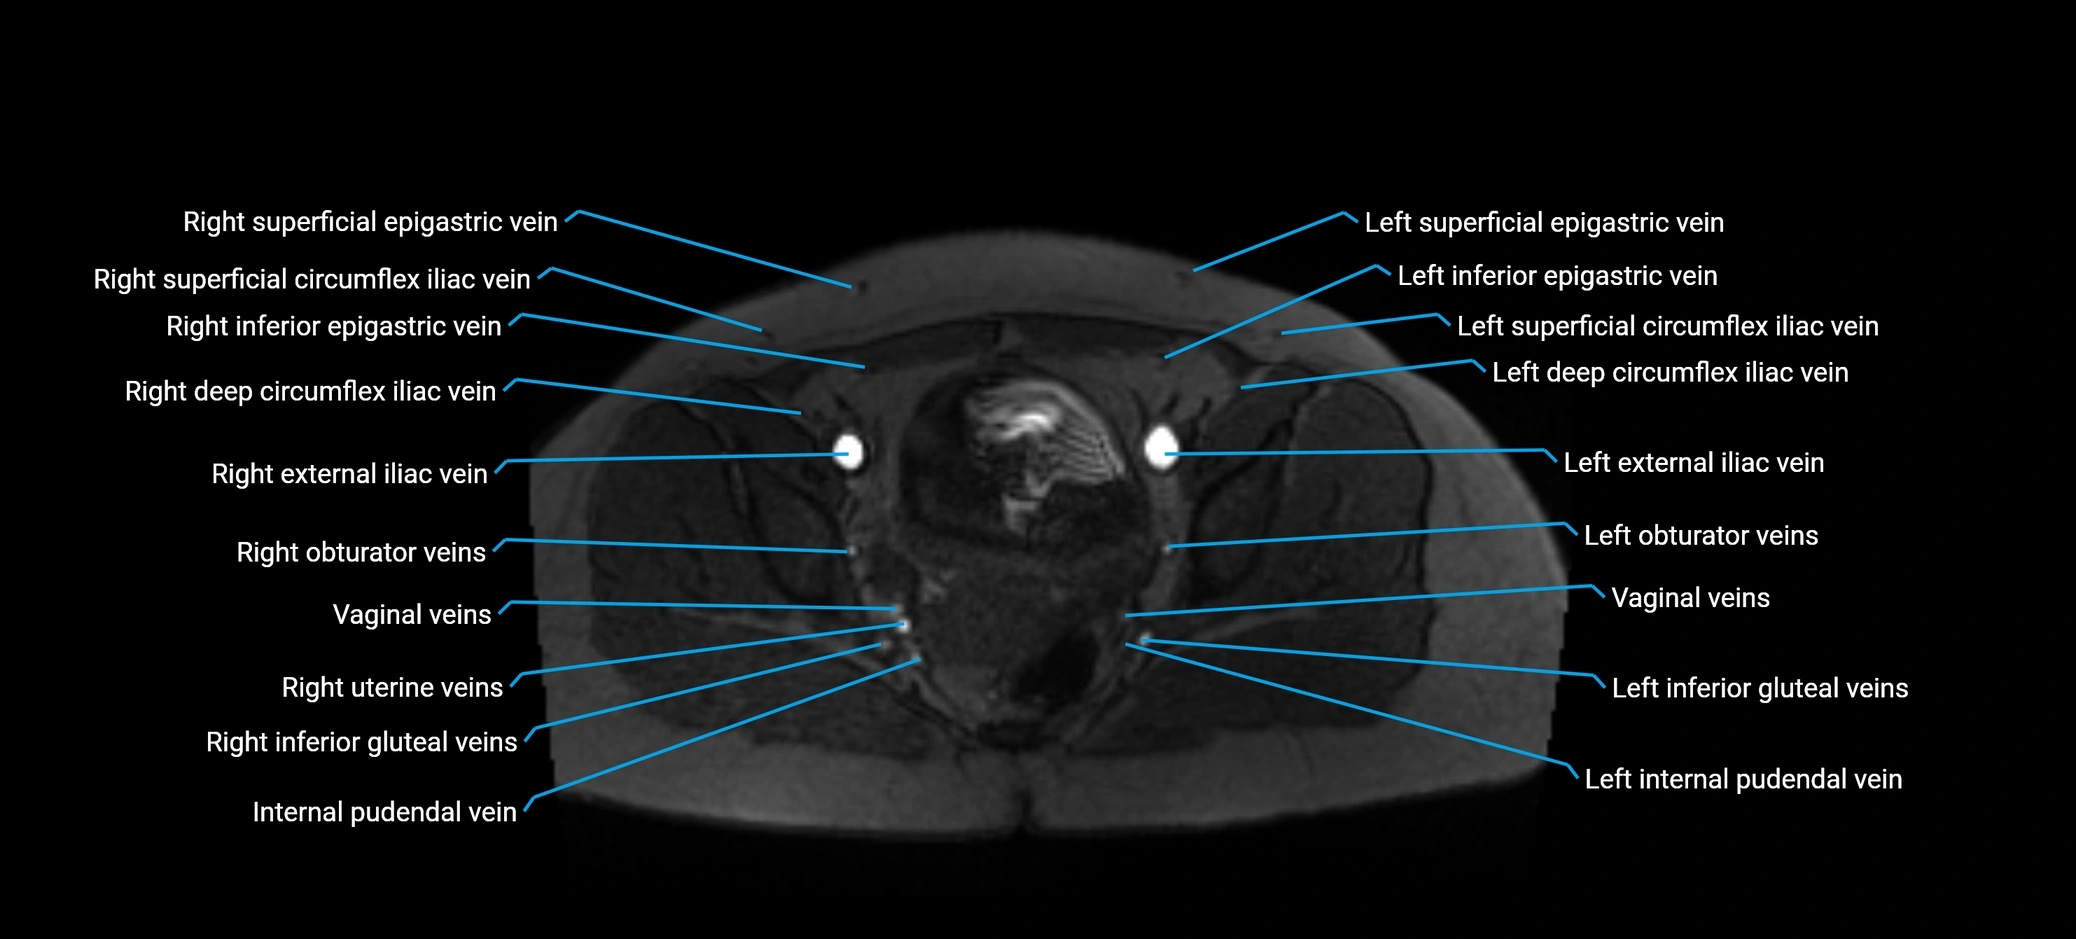

MRI image

image